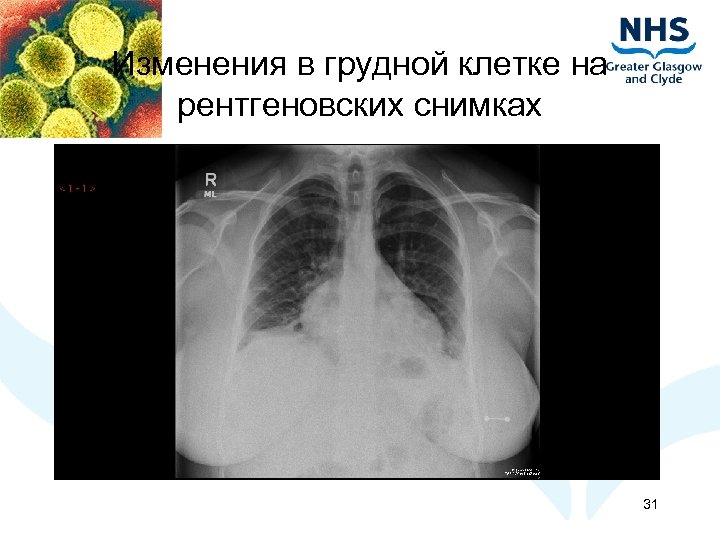

Изменения в грудной клетке на рентгеновских снимках 31

Изменения в грудной клетке на рентгеновских снимках 32

Изменения в грудной клетке на рентгеновских снимках 33